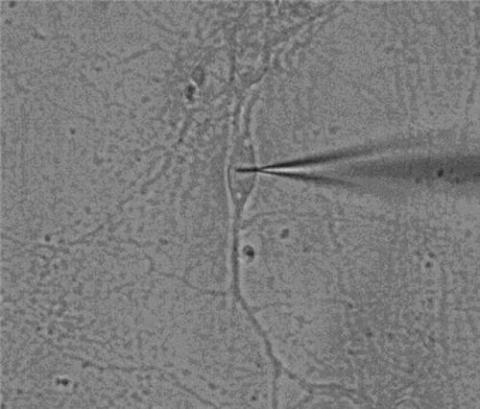

연구팀은 구리이온과 반응해 빛의 형광을 변화시키는 나노선 탐침을 개발했다.

빛으로 세포와 미세한 광학 신호를 직접 주고받도록 하고 빛이 산란 또는 흡수되는 현상을 최소화해 세포 속 구리이온의 정량분석에 성공했다.